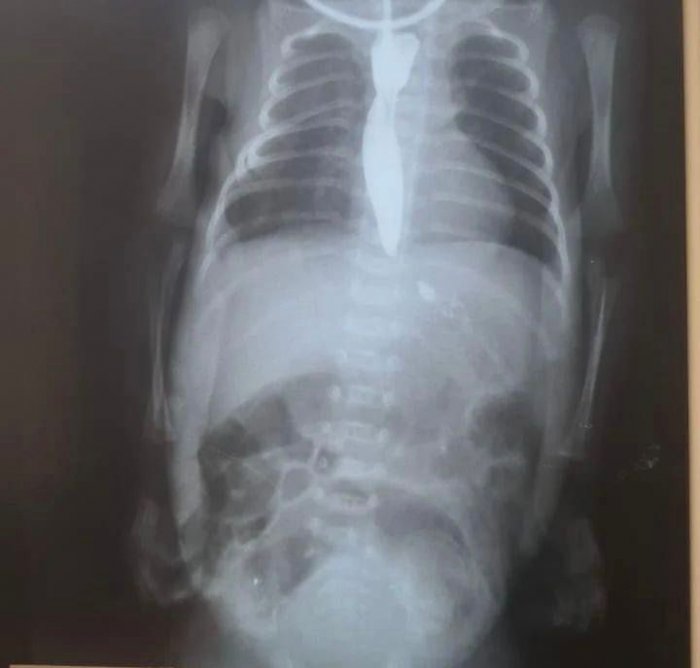

В Актау проведена операция на пищеводе новорождённого

В Мангистауском областном перинатальном центре «Мать и дитя» врачи провели сложную операцию на пищеводе новорождённого ребёнка, сообщает Центр общественных коммуникаций.

По словам детского хирурга Курмана Кайранова, оперировавшего малыша, ребёнок родился с аномалией - закупоркой пищевода. Для проведения операции малютке была вскрыта грудная клетка. Операция длилась полтора часа.

- Малыш весит один килограмм 500 граммов. Мы впервые сделали надрез ребёнку с таким малым весом. Благодаря квалифицированным специалистам ребёнок хорошо перенёс длительную операцию, - рассказал Курман Кайранов.